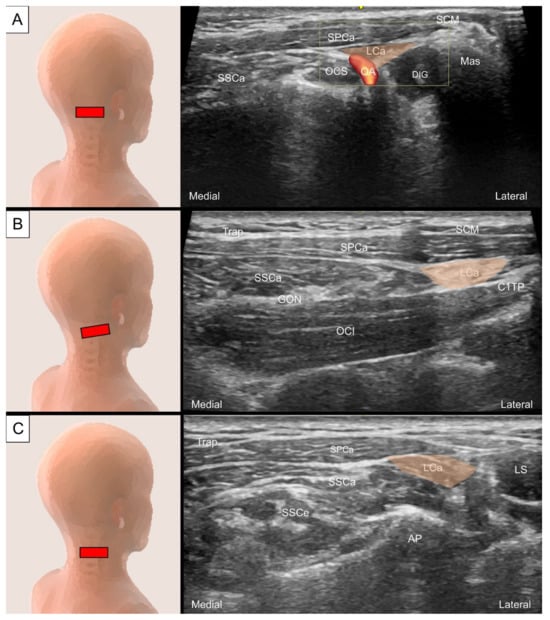

6.1. Sub-Occipital Muscles

6.1.1. Anatomy

6.1.2. Sonographic Scanning

6.1.3. Clinical Relevance